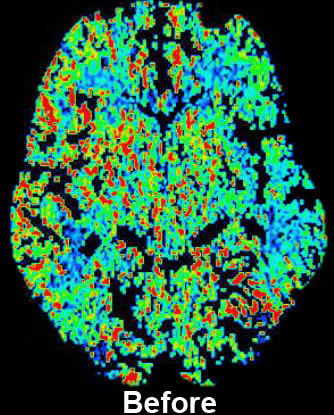

CT Perfusion with Diamox scan for Radiology- Before

How it works: CT perfusion with acetazolamide (Diamox) consists of a baseline CT perfusion scan of a portion of the brain, followed by injection of acetazolamide (a vasodilatory agent), and then a post acetazolamide CT perfusion scan of the same area. Normally, if blood flow to the brain is decreased, the vessels for that area will expand to maintain adequate oxygen flow, up to a maximum limit. The extent to which this can occur beyond baseline is the cerebrovascular reserve. CT Perfusion with acetazolamide allows assessment of the cerebrovascular reserve.

Equipment: Perfusion studies are usually performed on a Philips 64 or 256 channel CT scanner. OHSU is an ACR accredited CT facility.

Benefits: The study is used to evaluate cerebrovascular reserve, which can help determine the risk of future stroke. The study is often used to help determine which patients might benefit from interventions designed to increase blood flow beyond a very narrow or occluded vessel.

CT Perfusion with Diamox scan for Radiology- After

Exam Preparation: Exam preparation is the same as for a CT perfusion study, with additional screening for any potential contraindications to acetazolamide. Additional lab work of sodium and potassium levels are necessary if not performed within two weeks. Potential contraindications to acetazolamide include: Sulfa/sulonamides, severe renal dysfunction, cirrhosis/severe liver disease, adrenocortical insufficiency, hyponatremia, and hypokalemia. A nurse or technologist will interview you for contraindications, and an IV will be placed. Usually labs will be needed prior to the study.

What to Expect: A baseline perfusion scan is performed, followed by injection of acetazolamide over several minutes. It takes about 15 minutes for acetazolamide to have its maximal effect. A post acetazolimde perfusion scan is performed about 15 minutes after injection. Because of this time between scans and the additional time necessary for screening and possible lab work, the amount of time spent in the department will likely be between 1 and 2 hours.

Severe reactions to a single dose of acetazolamide are rare; however, more common reactions that are usually self limited can include brief numbness around the mouth, paresthesias, malaise, and headache.

Adverse reactions to contrast materials are uncommon, but can range from mild to severe. Severe reactions very uncommon. Further information about the risks and benefits of x-rays and contrast material can be found here.

Content by Dr. Louis P. Riccelli